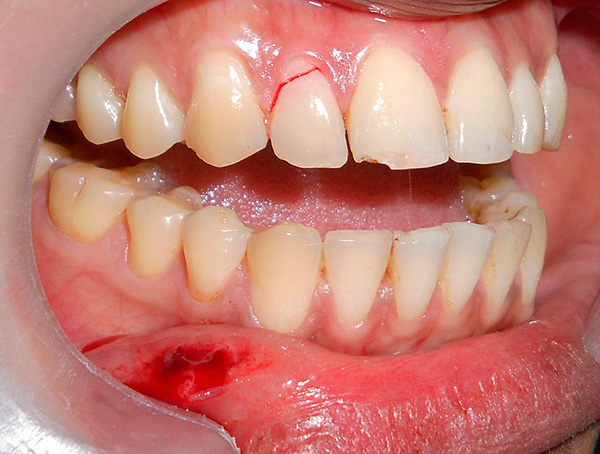

Le fotografie seguenti mostrano un esempio di impianto di un dente anteriore appena rimosso (che si è rotto da una lesione meccanica):

nota

In alcune situazioni, quando le condizioni del tessuto osseo lo consentono e l'impianto ha una fissazione primaria abbastanza buona, è possibile installare una corona in metallo-plastica economica per il periodo di osteointegrazione dell'impianto. Per i denti anteriori, questo è particolarmente importante, poiché consente di ripristinare l'estetica della dentatura in modalità express. Considerando che i denti anteriori non sono coinvolti nella masticazione del cibo, il carico sull'impianto sarà minimo.